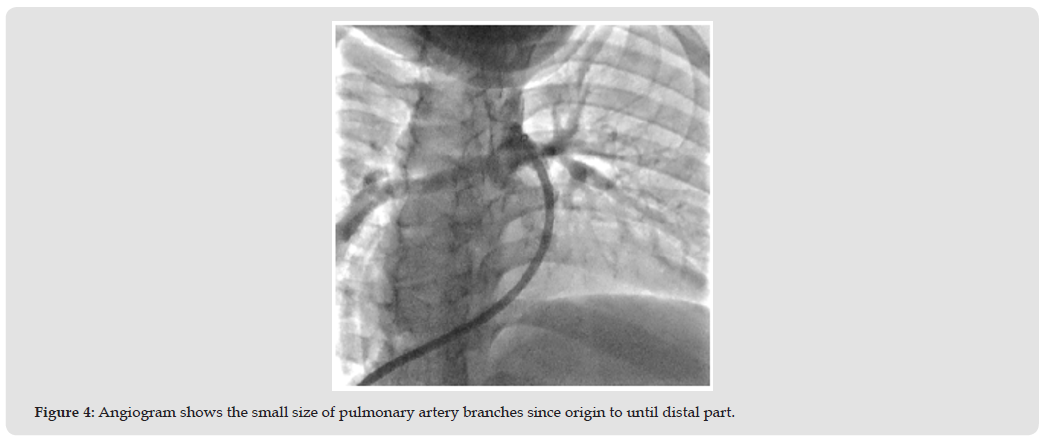

But the better property of echocardiography consist of inexpensively, non-invasively, portability and radiation safety, promote echocardiography popular equipment of imaging [4]. The Alagille syndrome and biliary atresia or liver cirrhotic most often cause patients to have liver enlargement [5] This condition is an obstacle to echocardiography in the parasternal area because it will cause the apex to be raised, resulting in difficult images adjust. This condition is also a limitation of examination in the subcostal view, Because the liver is enlarge and the tissue changes, it has a hard appearance, making it impossible to apply pressure to produce a clear image. [6] (Figure 3) The angiogram was used in case of need evaluated pulmonary hypertension and the role of intervention. (Figure 4).